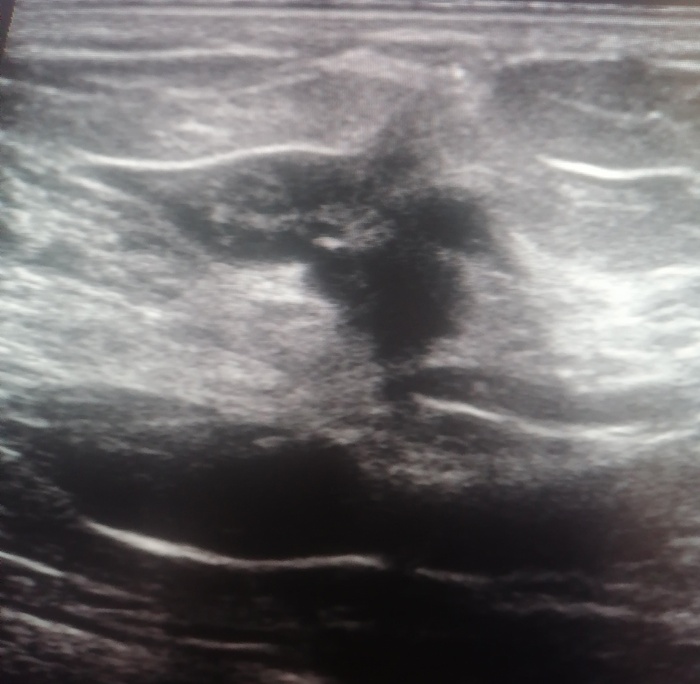

Не совсем типичный рак на УЗИ молочной железы

Всем привет, давно ничего не писал - было крайне лень. Этот пост будет интересен прежде всего врачам УЗД, конечно, ну и еще может врачам-онкологам и маммологам. На днях как обычно работал, и у одной пациентки обнаружилась интересная картина, достаточно нетипичная, если оценивать её с точки зрения УЗИ-признаков рака молочной железы. За несколько лет работы в онкологическом диспансере такое я вижу всего второй раз.

Итак, вот как оно выглядело:

Казалось бы, неровные, нечеткие, лучистые контуры, что необычного? Да просто оно по эхогенности ближе к окружающей ее фиброзной ткани, то есть, белое, яркое, если говорить простым человеческим языком. И его достаточно легко пропустить на УЗИ. Я его увидел только благодаря сердцевинке, которая была более темной, хотя на данном снимке это не особо заметно.